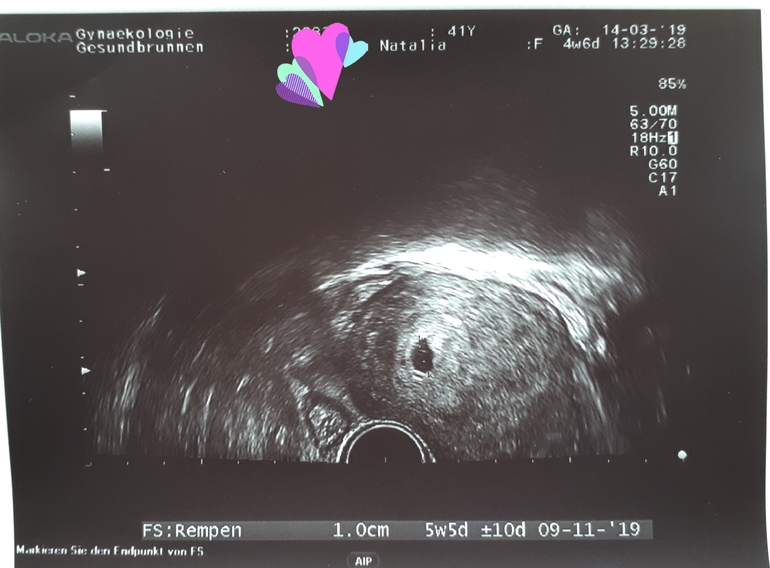

У врача на узи ПЯ 3,9мм и ХГЧ почти 6000

21дпо или 4 недели 6 дней